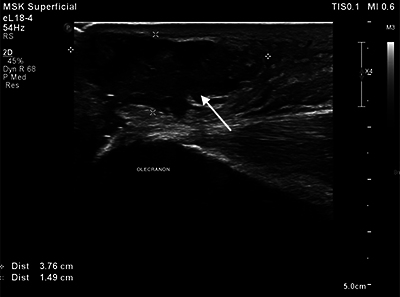

教学要点:强调在肌肉骨骼超声中识别镜像伪影的重要性,以避免误诊、不必要的干预和额外的诊断程序,从而导致患者焦虑、医疗费用增加和潜在的伤害。

Teaching point: To emphasize the importance of recognizing mirror image artifacts in musculoskeletal ultrasound to avoid misdiagnosis, unnecessary interventions, and additional diagnostic procedures that can lead to patient anxiety, increased healthcare costs, and potential harm.